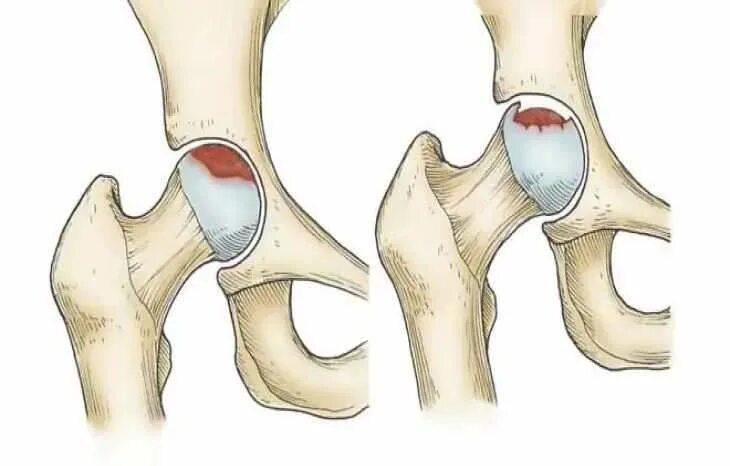

Некроз тазобедренного сустава лечение без операции